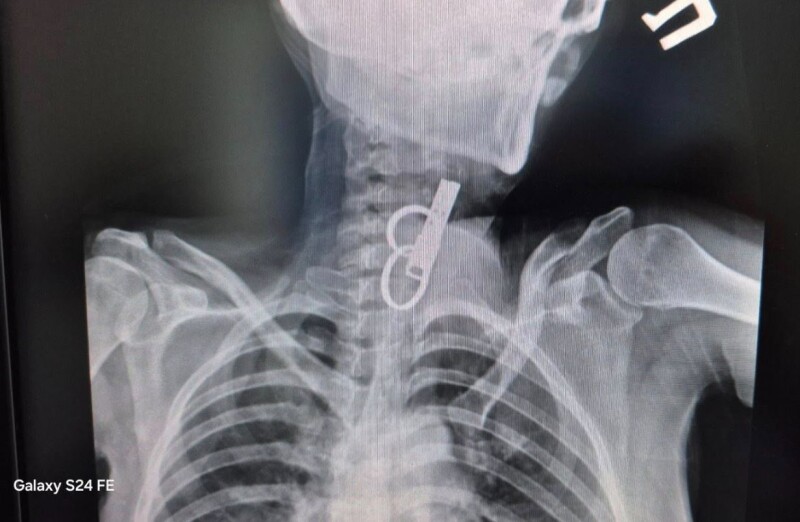

Жінка впродовж тижня ходила з ключем у стравоході.

У селищі Гусятин Чортківського району Тернопільської області лікарі врятували життя 40-річній пацієнтці. З її стравоходу витягнули дверний ключ. Вона його проковтнула, щоб не пускати родичів у хату

До лікарні пацієнтка потрапила в шоковому стані. Медики встигли діагностували причину й оперативно провели операцію за допомогою ендоскопа без жодного розрізу.

Пацієнтка перебувала в дуже важкому стані, адже ще до госпіталізації вона близько тижня ходила з проковтнутим ключем. Її родичі розповіли, що вона відмовлялася їсти, дуже погано почувалася, але що з нею сталося – не зізнавалася.

«Це дуже показовий випадок, що нам вдалося її врятувати. Як свідчить практика, переважно такі хворі гинуть. Спочатку ми не могли зрозуміти, що застрягло у стравоході. Це були якісь металеві кільця, які стояли зверху, а далі було ще якесь чужорідне тіло. Я здогадався, що це може бути ключ від дверей і почав його обережно витягувати», – розповів хірург-ендоскопіст комунального підприємства «Гусятинська комунальна лікарня» Олександр Садовий у коментарі ZAXID.NET.

Жінка впродовж тижня ходила з ключем у стравоході. Фото: «Гусятинська комунальна лікарня».

Ось через ці ключі, які опинилися в стравоході, жінка була за крок від смерті. Фото: «Гусятинська комунальна лікарня».